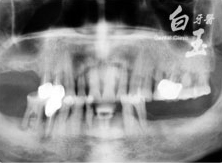

患者全口 X 光

治療前